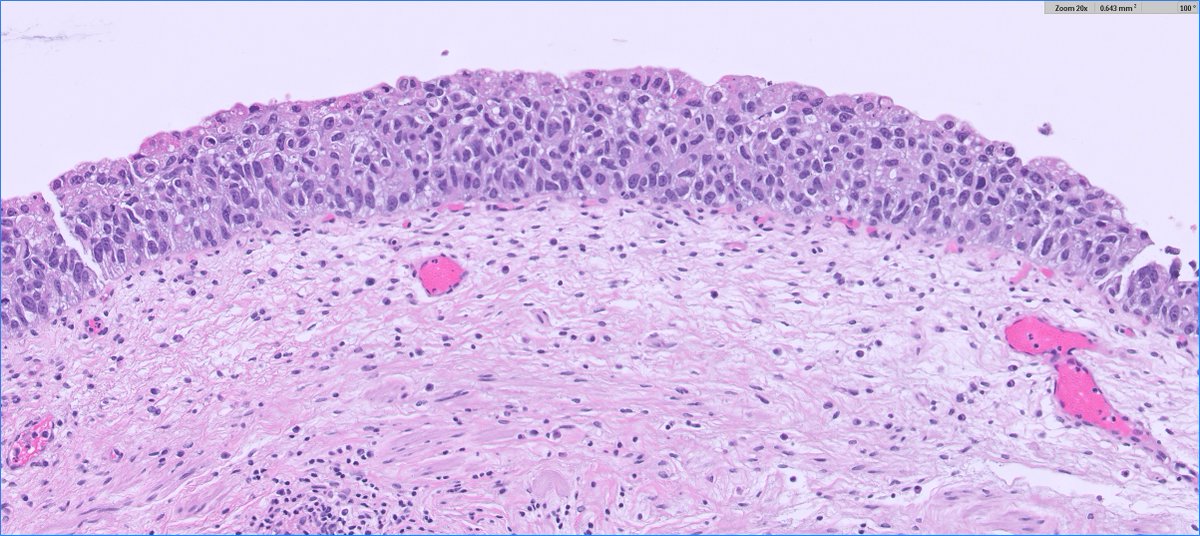

*** Case of the Month *** Bladder lesion in an 80 yr old female patient Contributors : Ronniel Morais Albuquerque Daniel Athanazio FB: GU Pathology Society IG: gu_pathology_society LinkedIN: GUPS Society Bluesky: https://t.co/1hR9PHdTaG

https://t.co/ijDfT9Juld

*** Case Of the Month*** Exophytic bladder tumour Contributors : Laurence A Galea, Sree Appu https://t.co/JVOZ1NQ8Mf

#GUPSCOW #GUpath #pathology FB: GU Pathology Society IG: gu_pathology_society LinkedIN: GUPS Society Bluesky: https://t.co/1hR9PHdTaG